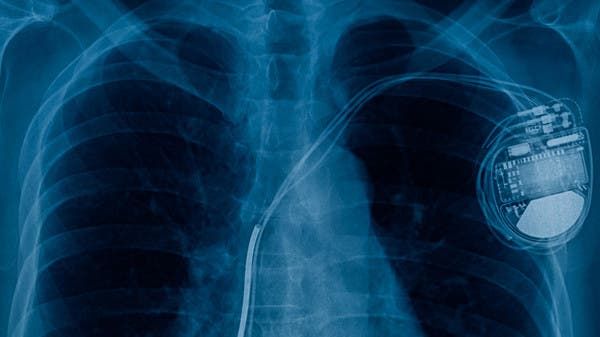

طوّر علماء أميركيون أول جهاز لاسلكي لتنظيم ضربات القلب في العالم، خالٍ من البطاريات، وقابل للزرع بالكامل ويذوب في الجسم عندما لا تكون هناك حاجة إليه.

ويجمّع الجهاز الطاقة لاسلكياً من هوائي عن بعد، وهو مصنوع من مواد متوافقة بيولوجياً يتم امتصاصها بشكل طبيعي في الجسم على مدار خمسة إلى سبعة أسابيع، وفقا لما نشرته "ديلي ميل" البريطانية.

إلى ذلك، يأمل فريق الباحثين من جامعتي نورث وسترن وجورج واشنطن في أن يتم استخدام الجهاز المبتكر قريباً بدلاً من أجهزة تنظيم ضربات القلب المؤقتة، والتي تتطلب إجراء جراحة لإزالتها.

كما، يعتمد الجهاز على جمع الطاقة لاسلكياً من هوائي خارجي باستخدام بروتوكولات الاتصال بالمجال القريب، وهي ذات التقنية المستخدمة للمدفوعات الإلكترونية في الهواتف الذكية، ما يلغي الحاجة إلى البطاريات الضخمة أو أي مكونات صلبة أو أسلاك.

جهاز تنظيم دقات عضلة القلب (ديلي ميل)

من جهته، قال جون روجرز، الباحث الرئيسي في الدراسة: إن "الأجهزة الموضوعة في القلب أو بالقرب منه يحتمل أن تتسبب في مخاطر الإصابة بعدوى أو أي مضاعفات أخرى، إلا أن أجهزة تنظيم ضربات القلب اللاسلكية تتلافى العيوب الرئيسية للأجهزة المؤقتة التقليدية.

وأوضح أن الجهاز الجديد "لا يعتمد على توصيل خيوط عبر الجلد من أجل إزالتها جراحياً بعد انقضاء الحاجة منها، وبالتالي تعطي مزايا إضافية مثل خفض التكاليف وتحسين النتائج في رعاية المرضى".

"قابلة للذوبان"وتتطلب الأجهزة المستخدمة حالياً خياطتها على عضلة القلب من خلال الجراحة ومن ثم إزالتها بعملية أخرى، وهو الأمر الذي يثير القلق من احتمال أن يؤدي إلى مضاعفات تشمل العدوى وتلف الأنسجة والجلطات الدموية.

في المقابل، لا يتطلب الجهاز الجديد سوى عملية جراحية لزراعته - وفي المستقبل سيمكن إدخاله من خلال وريد في الساق أو الذراع.

صورة توضع الجلطة القلبية الحادة للمريض

وسيتم زرع الدائرة مباشرة على سطح القلب ويمكن تفعيلها عن بعد، ثم يبدأ الجهاز، على مدى الأسابيع التالية، في الذوبان أو التحلل من تلقاء نفسه، وبالتالي لا يوجد ثمة حاجة إلى الإزالة الفيزيائية لأقطاب جهاز تنظيم ضربات القلب.

وقال فريق الباحثين إنه من خلال تغيير تكوين وسمك الجهاز، سيمكن التحكم في العدد الدقيق للأيام التي يظل فيها الجهاز يعمل قبل أن يتحلل. وسيمكن تصميم أجهزة تناسب مجموعة واسعة من الفترات الزمنية المطلوبة والمحتملة.